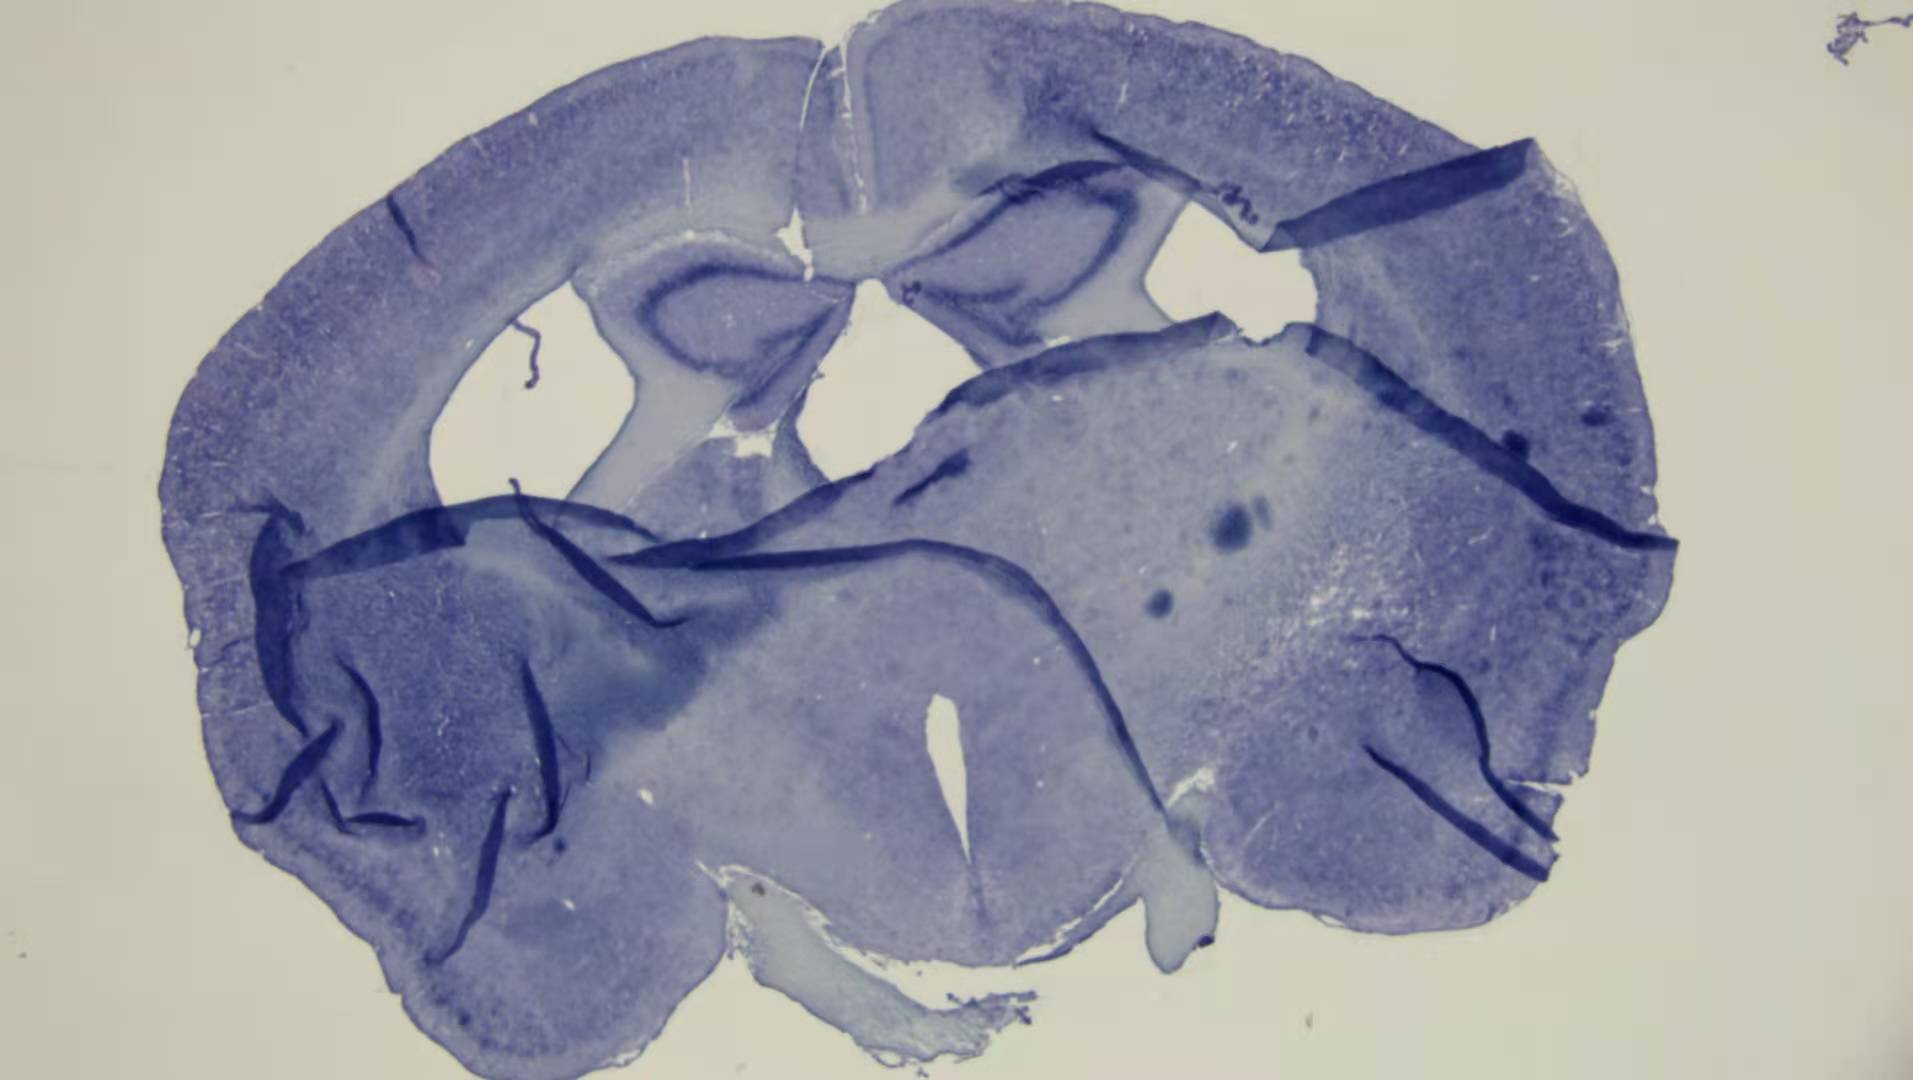

研究級多重熒光數(shù)字切片掃描系統(tǒng),可以實現(xiàn)1-5片熒光切片掃描樣品多重熒光的掃描拼接以及疊加功能;包括自動對焦、自動掃描、宏觀拍攝、樣品數(shù)據(jù)庫保存、定位導航檢索等功能,可應用于病理學、細胞生物學、科研和教育行業(yè)。

長壽命大功率LED照明裝置;8孔位電動熒光轉(zhuǎn)盤,最多可選擇8組不同的熒光波段;搭配20X/40X兩個高級APO復消色差物鏡,成像質(zhì)量高;閱圖模塊和電動平臺聯(lián)動,點擊圖像異常位置電動平臺位移到對應區(qū)域,方便對比核對。

MultiScan多重熒光掃描軟件, 通過電動載物臺、 自動對焦和智能化熒光成像結(jié)合, 實現(xiàn)多通道高質(zhì)量熒光掃描成像和超高清圖像拼接;SlideScan閱片軟件是我司的專業(yè)級數(shù)字切片瀏覽器,使用先進的硬件加速技術(shù),讓超高分辨率的數(shù)字切片能毫無卡頓感地瀏覽和任意縮放,同時提供豐富的管理和處理功能,包含色彩平衡、定倍顯示等,多通道熒光自動疊加,疊加通道可任意勾選,提供API可獲取圖像數(shù)據(jù)底層RawData用千Al計算。